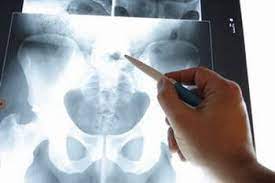

Bei Blockaden im Hüftgelenk oder bei einer ISG-Blockade kann über gezielte Manipulation durch Handgriffe des Arztes eine sofortige teilweise Linderung erzielt werden. Hüftschnupfen Coxitis fugax ist eine nicht-bakterielle Hüftgelenkentzündung die meist harmlos verläuft. Der normale Blutwert für Kalium bei Erwachsenen im Serum liegt zwischen 35 und 51 mmoll. Bei 15 bis 30 Prozent der Betroffenen wird die reaktive Arthritis allerdings chronisch. Das Hüftgelenk lateinisch Articulatio coxae Gelenk der Hüfte über frühneuhochdeutsch hüffte von althochdeutsch huffi dem Plural zu huf Hüfte die seitliche Körperpartie unterhalb der Taille ist nach dem Kniegelenk das zweitgrößte Gelenk der SäugetiereDer Oberschenkelknochen Femur und das Becken Pelvis bzw. Mit gesundheitsinformationde bieten wir Bürgerinnen und Bürgern unabhängige kostenlose und werbefreie Antworten auf häufige Gesundheitsfragen an. Die Schenkelhalsfraktur SHF Kurzform für Oberschenkelhalsbruch oder Oberschenkelhalsfraktur ist ein hüftgelenksnaher Knochenbruch Fraktur des Halses Collum vom Oberschenkelknochen FemurDiese Fraktur entsteht meist durch Sturz auf die Seite.